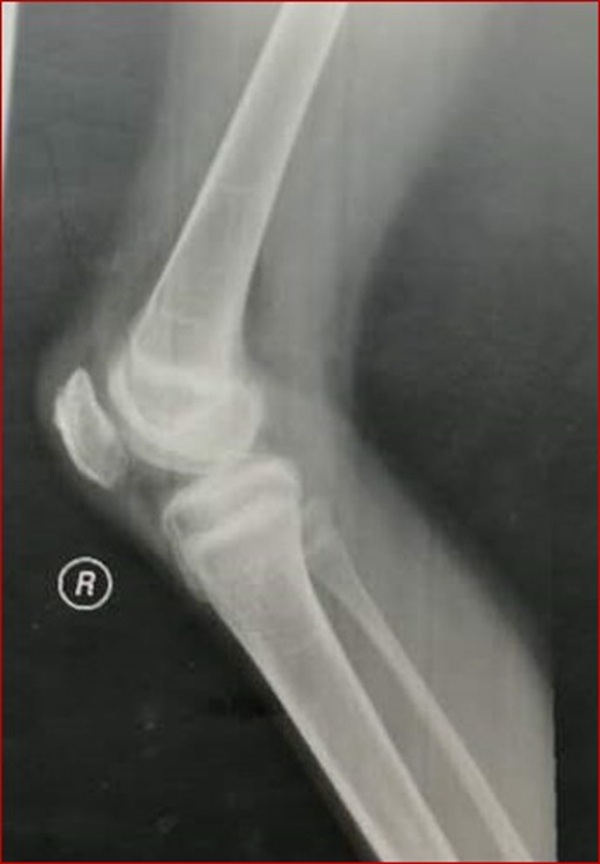

图2 受伤3周X线片